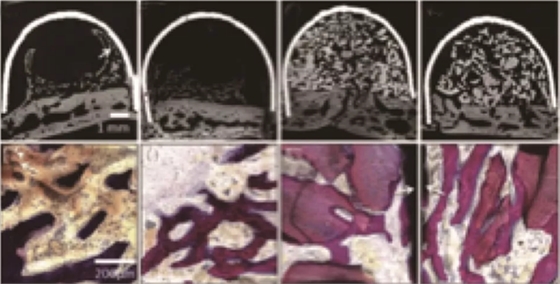

因?yàn)镻RF中含有生長(zhǎng)因子,而體外實(shí)驗(yàn)也證明了這些生長(zhǎng)因子具有一定的促進(jìn)成骨效果。學(xué)者也將其應(yīng)用到了促進(jìn)成骨的動(dòng)物實(shí)驗(yàn)中,Knapen等在兔的顱骨中研究了PRF的促進(jìn)成骨效果[5],結(jié)果在組織學(xué)和組織形態(tài)定量學(xué)的分析中(圖2、3)都沒能發(fā)現(xiàn)PRF有任何附加的影響。

Nejat在上頜竇外提升術(shù)中研究了PRF促進(jìn)成骨的效果[6],在實(shí)驗(yàn)中對(duì)照單獨(dú)使用Bio-oss和Bio-oss聯(lián)合PRF在上頜竇提升術(shù)中的應(yīng)用,在6個(gè)月的愈合期之后,對(duì)新生骨進(jìn)行組織學(xué)和組織形態(tài)定量分析(圖4),發(fā)現(xiàn)兩組沒有差異。這就說明了PRF的使用并不能帶來更多更好的成骨效果。